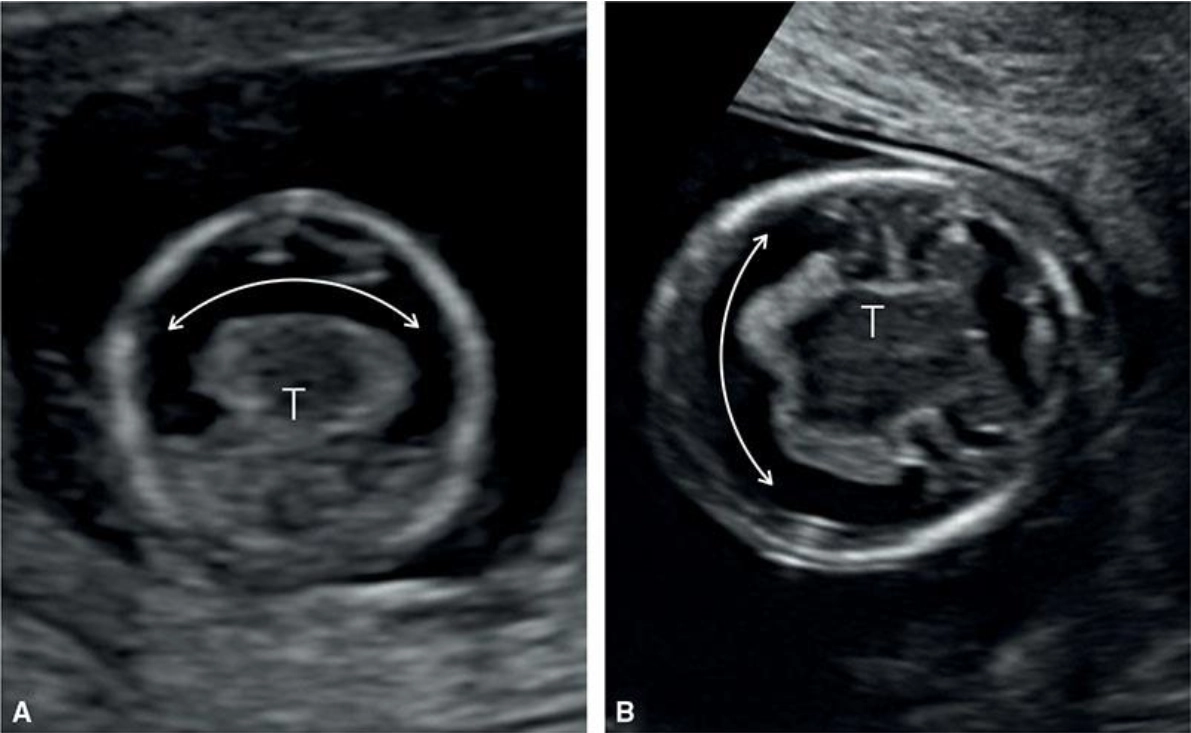

Não thất duy nhất (Holoprosencephaly-HPE)